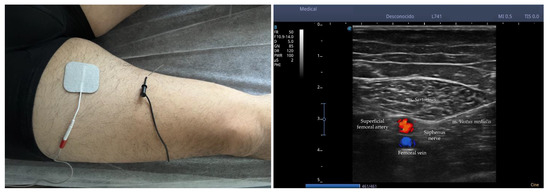

The identification of the nerve by ultrasound was carried out by a physical therapist with 10 years of experience following the method described by Riegler et al. (2018) using B-mode ultrasound imaging (4.2 to 13 MHz) coupled with a multifrequency linear array transducer, model 12L-RS (GE Logiq V2, GE Health Care, Chicago, IL, USA) [23]. Ultrasonography scanning began with the patient in supine position with knees straight placing the transducer in the horizontal plane to obtain a cross-sectional view of the m. sartorius (ST) and m. vastus medialis (VM) approximately 10 to 15 cm above the knee joint line. ST was shielded distally until reaching a tubular structure that pierces m. tensor fasciae latae (TFL) over the ST, and the nerve located in the fat pad is IPBSN. With the purpose of correctly assigning the IPBSN to the origin of the saphenous nerve, the former was traced proximally to its origin. The IPBSN is then traced distally, across the medial tibiofemoral joint line, until the branch divides into terminal branches. When detectable, all branches are followed until reaching their most distally visible part. Figure 2 shows the ultrasound nerve identification.

Figure 2. Ultrasound nerve identification. Note: During ultrasound identification of the saphenous nerve, the probe is positioned transversely on the medial aspect of the thigh following the course of the nerve distally. Before its division, the nerve is located at a crossroads comprised of the m. sartorius on the superficial plane, the m. vastus medialis on the medial side and surrounded by the femoral vein (blue) and the superficial femoral artery (red).